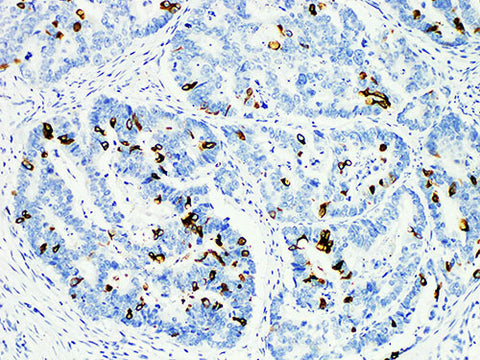

MUC2 Monoclonal Antibody Stored at 2~8°C

Applications IHC-P

Tissue Specificity Colon cancer

Mucoprotein 2 (MUC2) is a protein with a molecular weight of 520 kDa. In normal tissues, mucoprotein 2 is mainly expressed in the epithelium of small intestine, salivary gland and mammary gland, but not in other parts. It is mainly used in the study of colon cancer and gastric cancer.